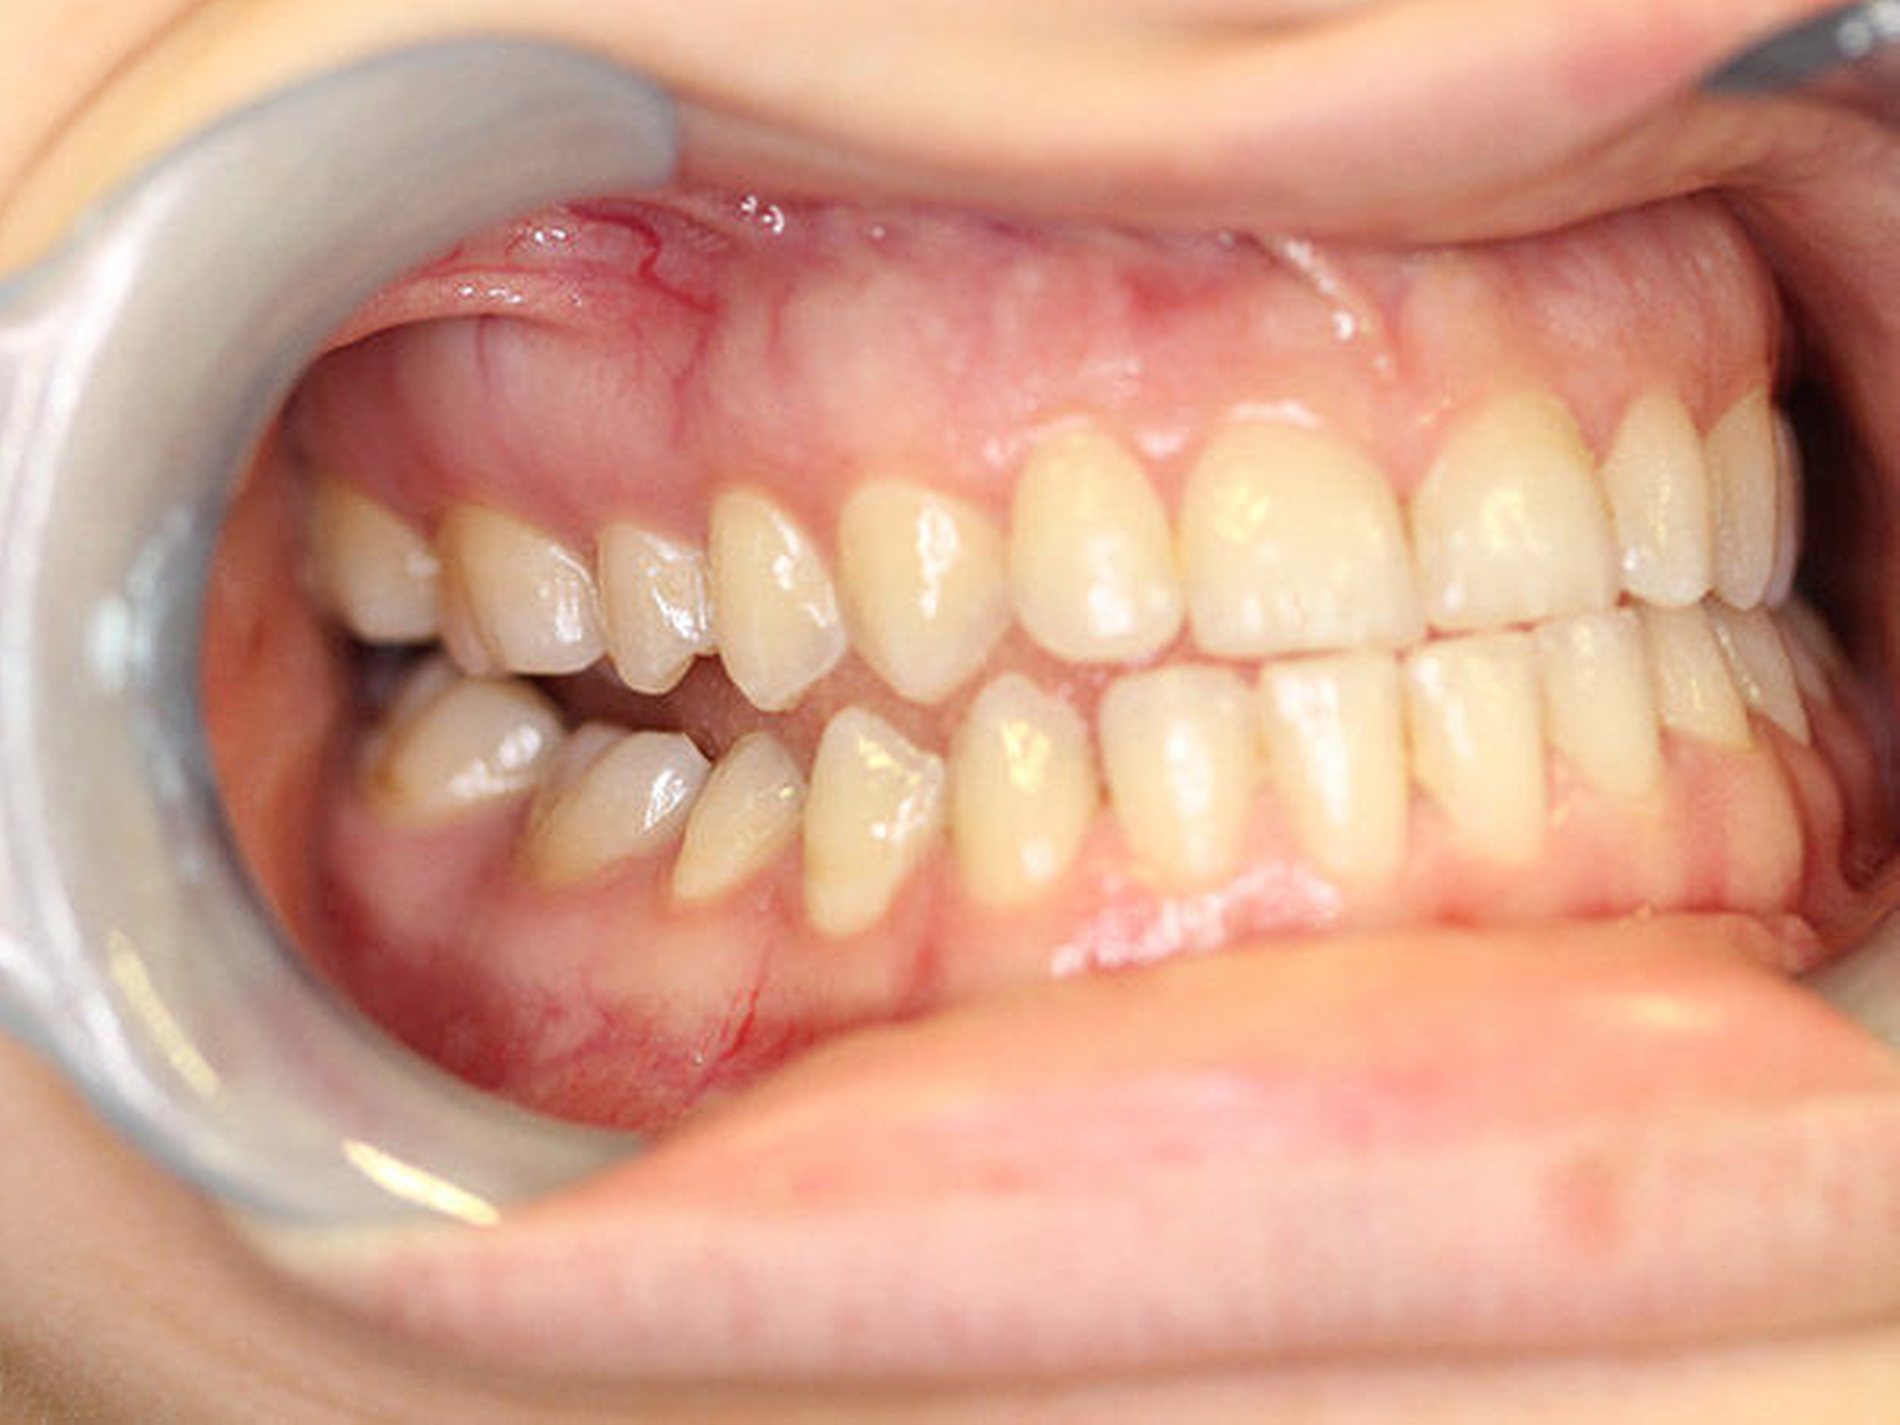

Intraoral fand sich eine Mesialbisslage von einer halben Prämolarenbreite im Seitenzahnbereich beidseits. Ein Kontakt bestand regio 16/47 mit Nonokklusion der restlichen ipsilateralen Eck- und Seitenzahnregion (Abbildung 2). In regio 11/41 fand sich eine Kreuzbisssituation, in regio 21/31 eine Kopfbisssituation. Die Unterkiefermittellinie war interessanterweise um 3 bis 4 mm nach rechts verschoben, das knöcherne Kinn hingegen nach links. Weitere faziale Fehlbildungen lagen nicht vor.